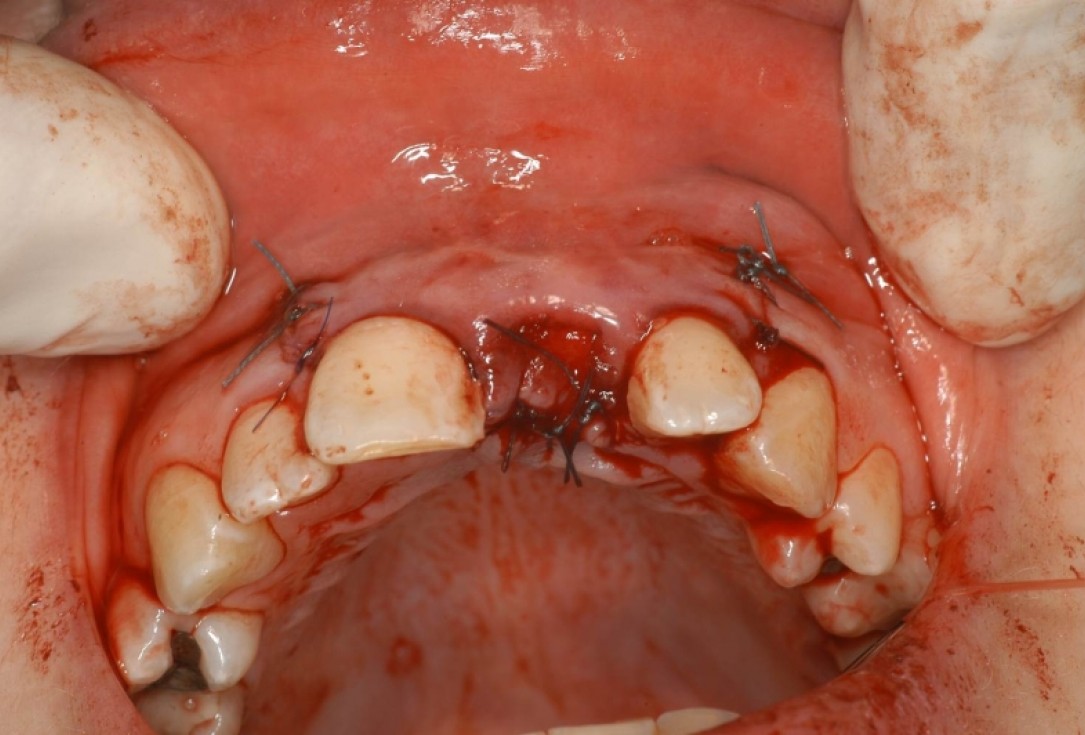

09/12 - Wound closure, occlusal viewTreatment of dehiscence defect with cerabone® & Jason® membrane - Dr. M. Steigmann